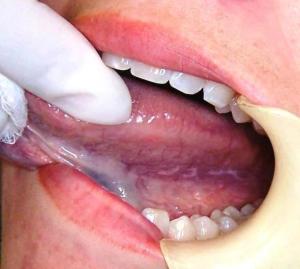

Lichen Planus

Lichen planus is a disease in which there is an itchy rash on the skin or in the mouth. The exact cause is not known, it is said to be due to an allergic or immune reaction.

Mouth lesion is: Tender or painful, Located on the sides of the tongue or the inside of the cheek. May be on the gums.